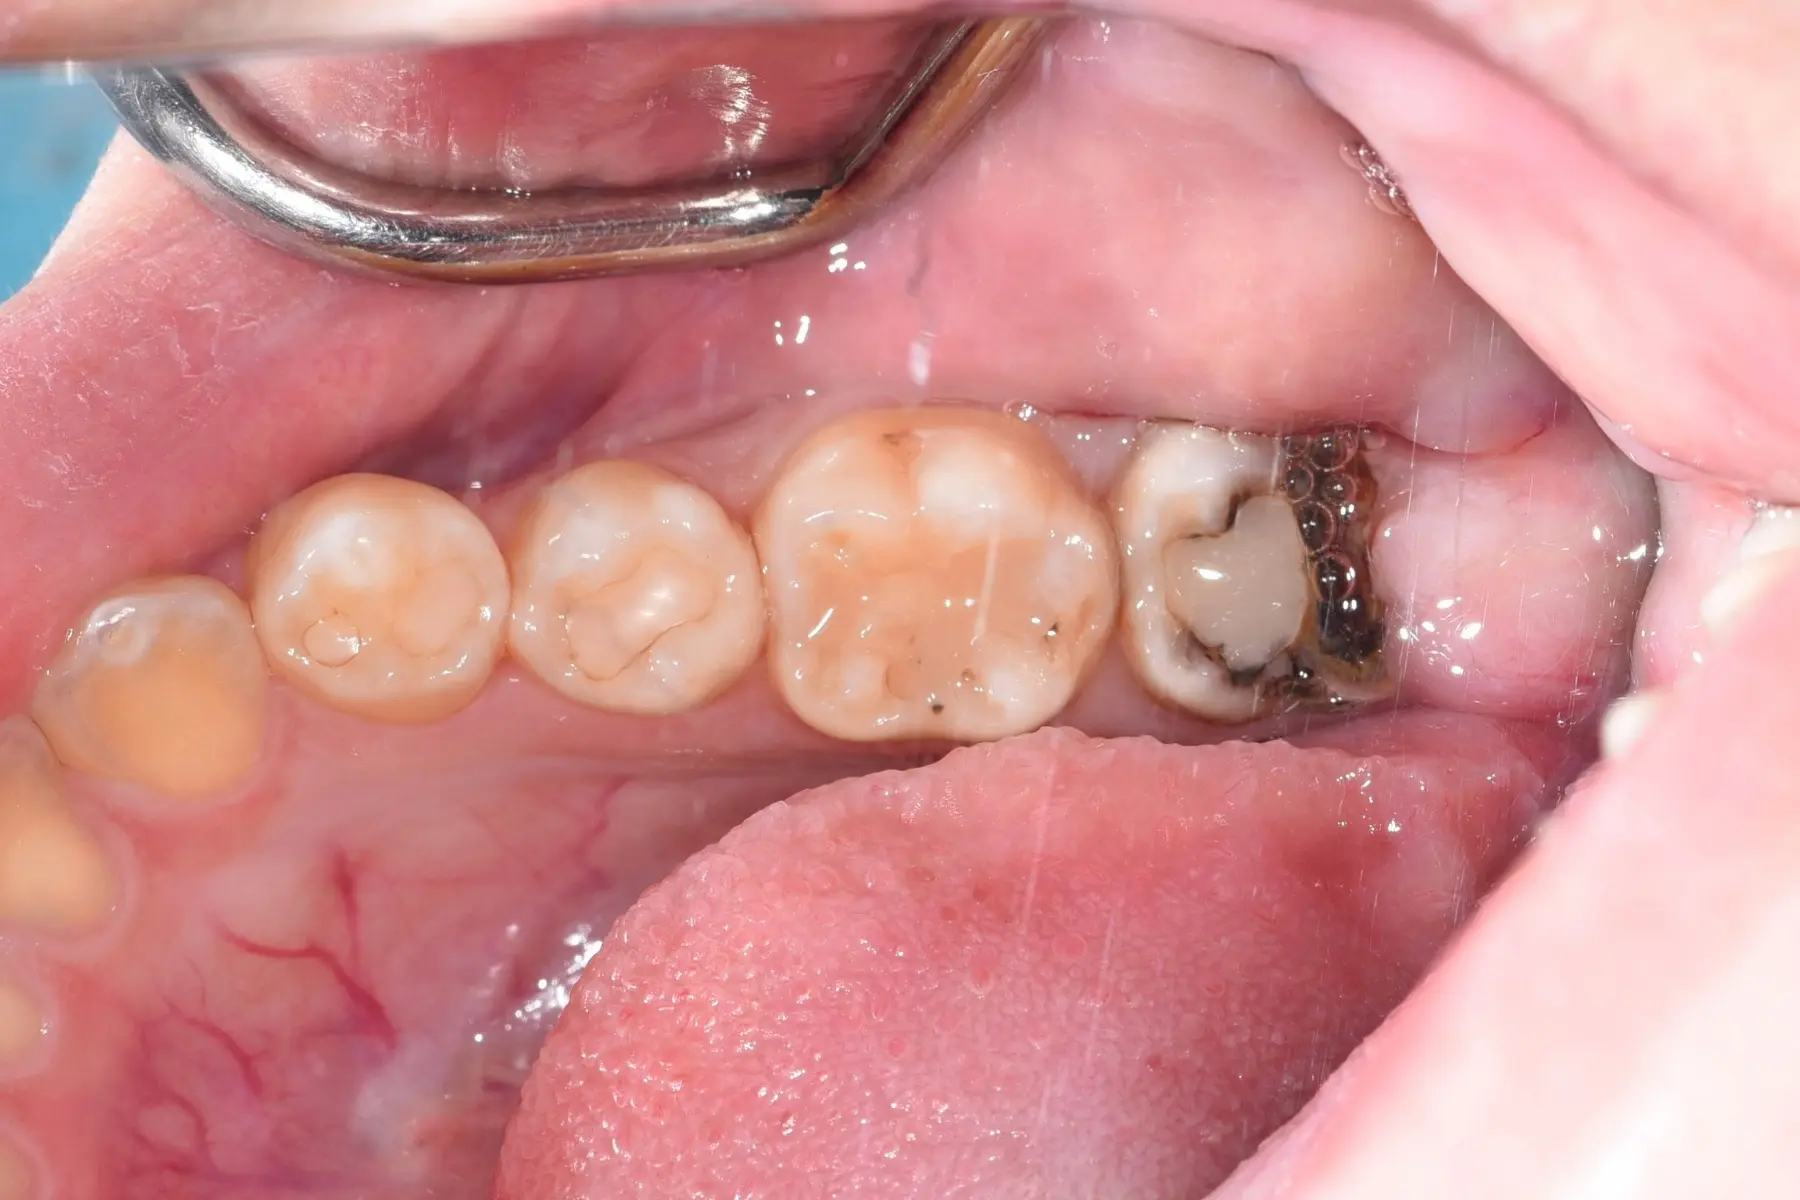

• 自體牙移植術前

自體牙移植術後

口腔外科/自體牙移植

主治醫師

• 林明志

治療時間

單次療程

主訴

矯正治療前發現牙齒嚴重蛀牙,無法保留